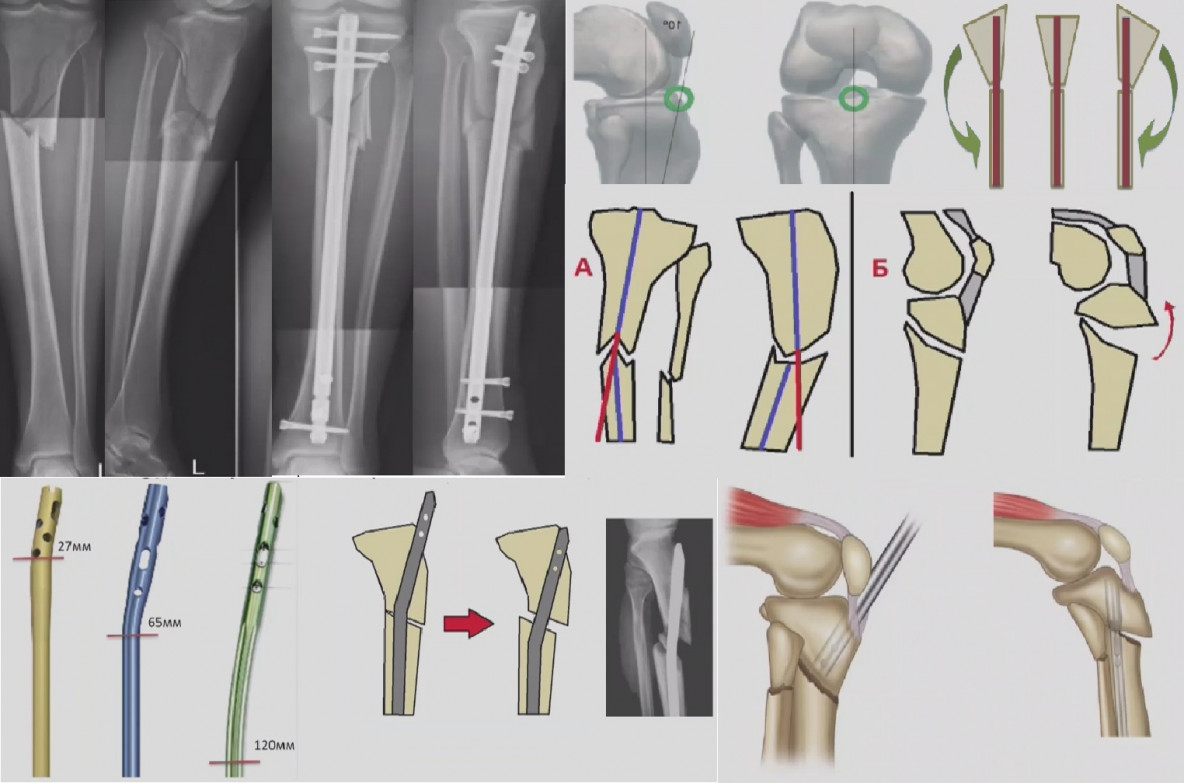

Интрамедуллярный остеосинтез проксимального отдела большеберцовой кости ...

Блокируемый интрамедуллярный остеосинтез (БИОС)